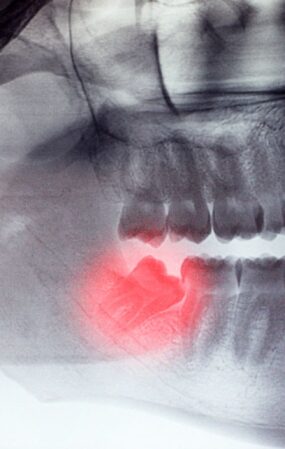

Tanı Koyma

Dişinizdeki vakanın teşhisini yapıyoruz.